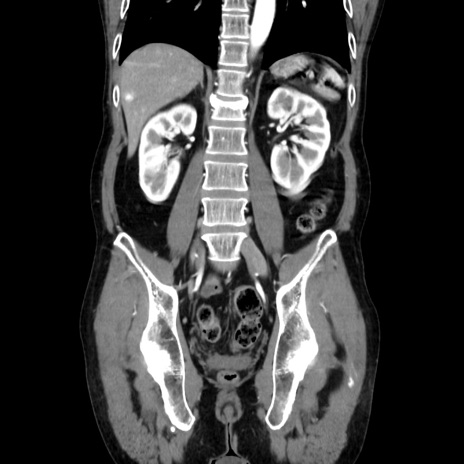

症例37(冠状断像)

【症例】40歳代 男性

【主訴】腹痛

【現病歴】4時間ほど前に電車に乗車中に臍部上より腹痛出現。徐々に増悪し起立困難となり、救急外来受診。生ものは数日食べていない。今朝お雑煮を食べた。

【身体所見】BT 36.8℃、BP 117/84mmHg、HR 91/min、SpO2 97%、苦悶様、腹部:臍上部広範囲圧痛あり、反跳痛±

【データ】WBC 8100、CRP 0.03